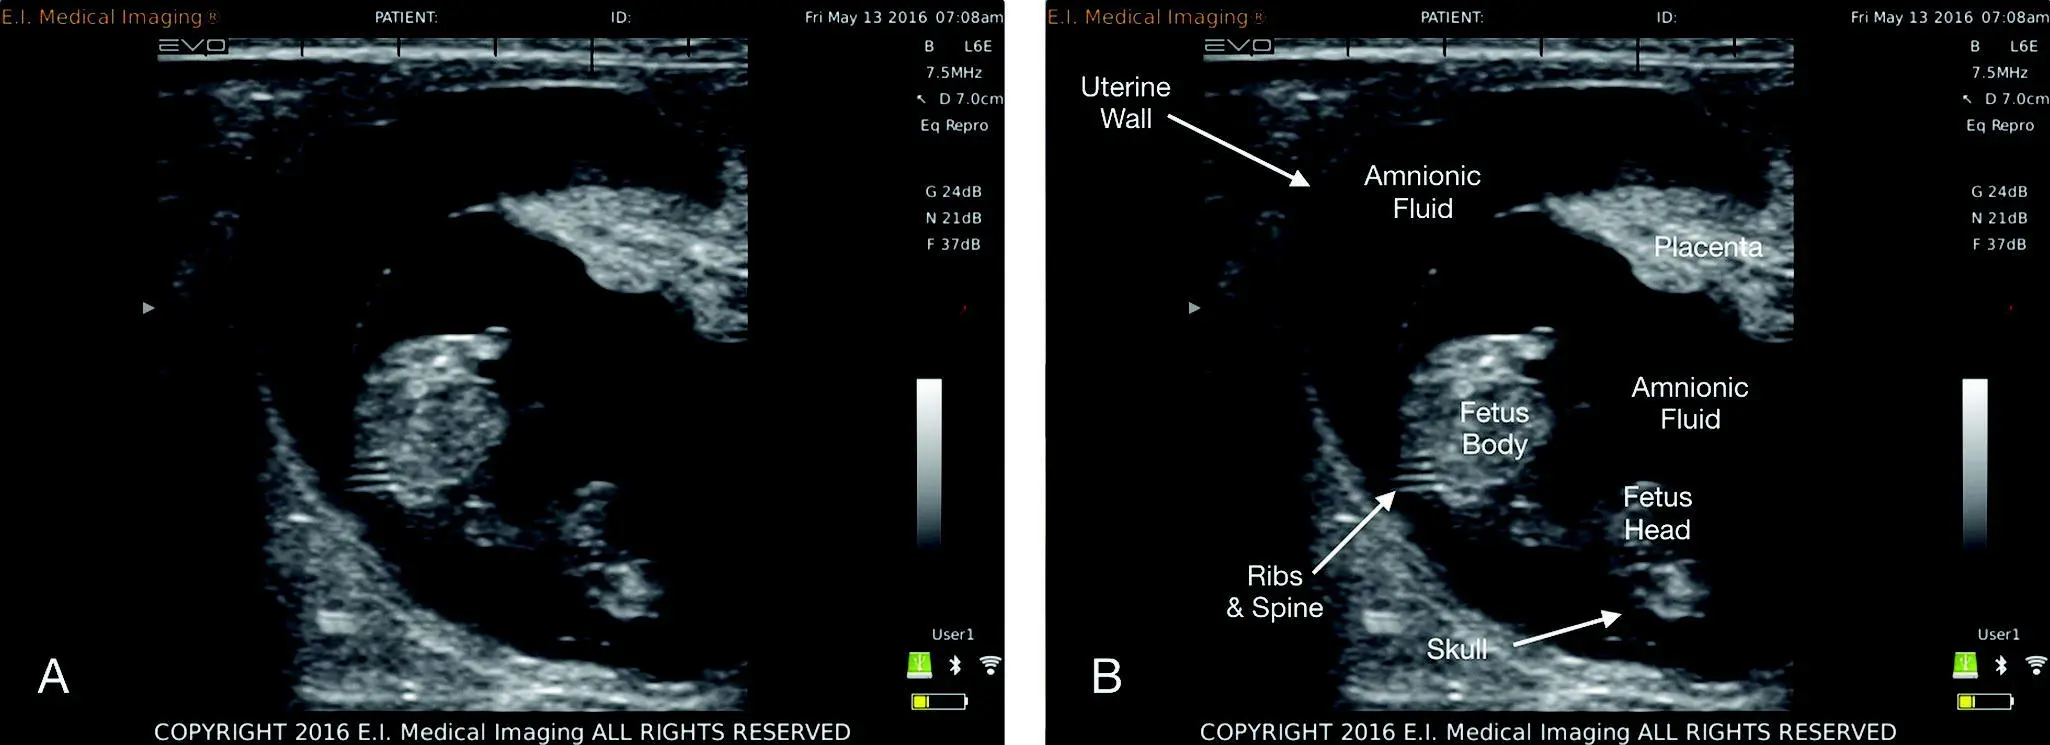

The jargon of ultrasound can be intimidating to the novice sonographer. Clarity may be accomplished through acknowledging that ultrasound is generally the opposite of how free fluid, air, and soft tissue appear on radiographic studies (our brain needs to reformat itself). For example and very simplistically, air is white on ultrasound and black on radiographs. Fluid is black on ultrasound and white on radiographs. However, bone is black (shadows) on ultrasound? And white on radiographs? Or white along its proximal surface with acoustic shadowing through the far field. Now if we are losing you, hang in there. The figures help ( Figures 1.2, 1.3, 1.4, 1.5). Study them now .

The ultrasound terms describing whites, grays, and blacks are anechoic (black), degrees of echogenicity (hypoechoic, shades of gray), and hyperechoic (white). The terms may be used relatively between structures like “X relative to Y” and “Y relative to Z.” For example, the spleen is hyper echoic (brighter than) to the left kidney. The liver is hypo echoic (darker than) to the falciform fat. The feline cortex of the kidney is isoechoic (same as) to the spleen (see Figure 1.3).

Figure 1.4. This figure is unlabeled and labeled for contrast of what tissue looks like in a gravid female, illustrating the different tissues and structures that correlate with concepts in Figures 1.1and 1.2. Image used with permission from E.I. Medical, Loveland, CO, USA. www.eimedical.com